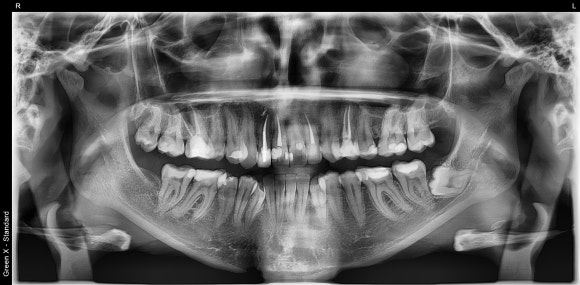

영국에서 거주중이신 이 환자분은,

오른쪽 아래 어금니를 치료 받으신 후

통증이 재발하셨다고 합니다.

한국에 거주하시는 분이 아니었기 때문에

출국 일정에 맞추느라고 조금 서둘러야했지요.

세 번째 내원만에 깨끗하고 완전한 치료를

할 수 있게 되었습니다.

치아 신경 협착이 심한 케이스였지만

세 번만에 불편감이 모두 사라지셔서

시간이 부족해서

크라운은 본국에 돌아가서 하시기로 했습니다.